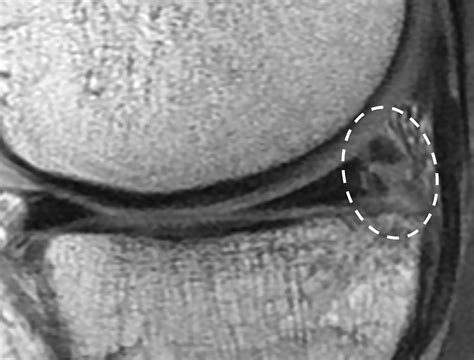

When looking at Torn Meniscus MRI pictures, the goal is to identify signal abnormalities within this cartilage structure. Healthy menisci appear as dark, triangular shapes on standard MRI sequences. When a tear is present, it disrupts this dark signal, allowing bright fluid or scar tissue to show up in the image.

Radiologists are trained to scrutinize the meniscus for specific patterns of signal intensity. A healthy meniscus should have low signal intensity (meaning it looks black on the MRI). A torn meniscus typically exhibits increased signal intensity (appearing white or bright) within the substance of the cartilage.

However, it is important to note that not all bright signals are tears. Sometimes, age-related degeneration can cause internal signal changes that do not actually represent a structural tear that requires surgery. A tear is definitively diagnosed when the high-signal intensity extends to the articular surface of the meniscus. When you see this on an MRI, it confirms that the cartilage has been compromised.

Not all tears look the same on an MRI. The shape and location of the tear heavily influence treatment recommendations. Common patterns seen on imaging include:

• Bucket Handle Tear: A severe type of longitudinal tear where the torn part of the meniscus flips into the center of the joint, often causing the knee to lock.

• Radial Tear: A tear that cuts across the meniscus perpendicular to its fibers, potentially disrupting its ability to absorb shock effectively.